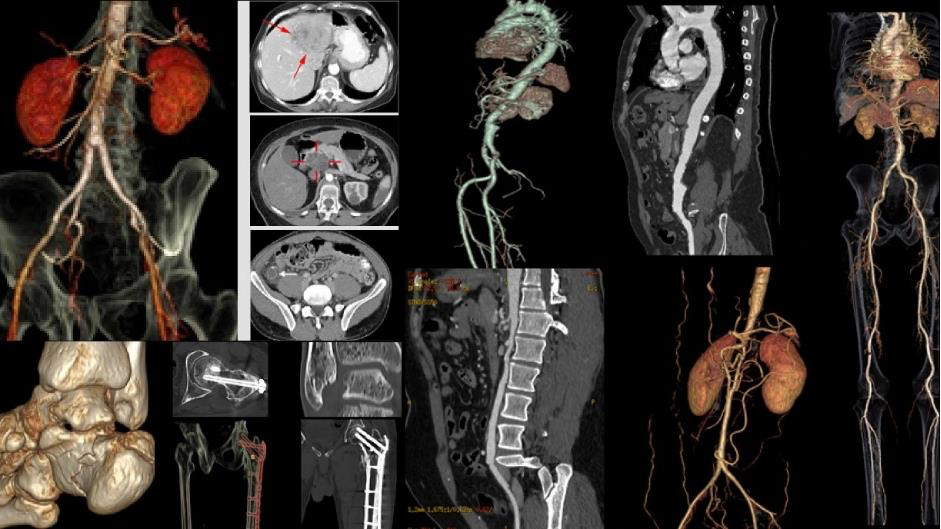

Hình ảnh học CT Scan tái hiện rõ nét các chi tiết bên trong cơ thể, giúp bác sĩ phát hiện sớm những tổn thương và nguy cơ bệnh lý tiềm ẩn

Mô hình Ningen Dock Bernard được phối hợp vận hành trạm chẩn đoán hình ảnh cùng bệnh viện Đại học Yamanashi (Nhật Bản), tất cả khách hàng thực hiện dịch vụ MRI, CT Scan, kết quả không chỉ được chuyên gia trong nước đọc mà còn được chuyển sang Khoa Chẩn đoán Hình ảnh Bệnh viện Đại học Yamanashi để đối chiếu, xác nhận. Nhờ đó khách hàng tại Việt Nam được tiếp cận chuẩn mực kiểm soát chất lượng tương đương Nhật Bản. .